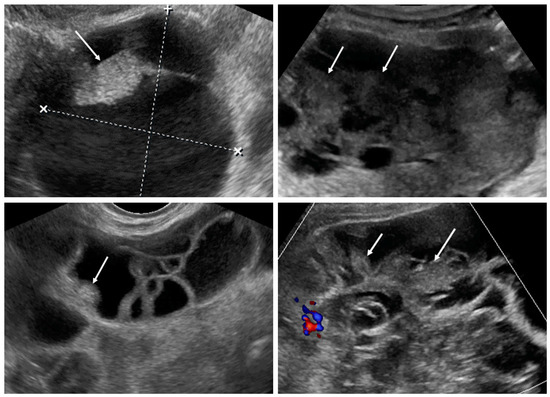

3.4. Decision Tree

The optimal decision tree was developed and validated using data from 162 patients, randomly divided into training (80%) and test (20%) sets. At input, all clinical and ultrasound data were used except cancer markers. The resulting tree is shown in Figure 6. For example, a patient with an adnexal mass who underwent CRC treatment in the past should be directly suspected of having a metastatic tumor (irrespective of ovarian tumor sonographic features). A patient without CRC in anamnesis who has a tumor of <40 mm should be suspected of having primary OC (0% risk of mCRC). A patient with an ovarian tumor of ≥40 mm with more than three papillations has an 88.9% probability of primary OC and an 11.1% risk of mCRC. A patient with a tumor of ≥40 mm, <3 papillations, and ≥6 locules has a 91.7% probability of having an ovarian mCRC, while those with <6 locules and metastases detected in the abdominal cavity should rather be suspected of having primary OC, although the risk of metastatic cancer remains at 29.6%. The AUC of this decision tree was 0.768.